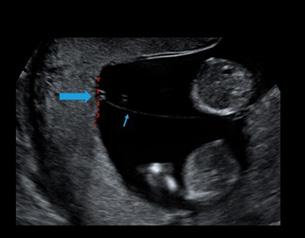

Certeza: La ecografía transvaginal es la prueba confirmatoria de embarazo. A las 4.5 semanas, se observa saco gestacional; a las 5 semanas, se encuentra embrión, y a las 6 semanas es posible auscultar los latidos cardiacos fetales con el doppler . También se considera la percepción de movimientos fetales por parte del médico.

Figura 11. Ecografía de I trimestre Examen de certeza para confirmar un embarazo eutópico y viable

Figura 18. El cordón umbilical Corte transversal del cordón umbilical a la ecografía donde se evidencia el “Signo de Mickey Mouse” (AU: arteria umbilical, VU: vena umbilical)